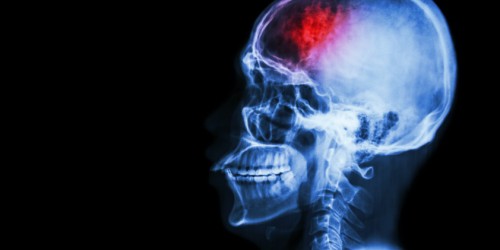

Hello. Yes, systemic sclerosis can affect inner organs. Digestive system is the most common location of these changes. There can be problems with swallowing of food. Since the movement of intestines is compromised, there can be problems with absorption of nutrients. There can also be problems with bowels, so one can expect problems with defecation. Blood vessels are also affected. As a result, there can be headaches or even stroke. Pulmonary hypertension is also a possibility. I hope this helps. Bye!